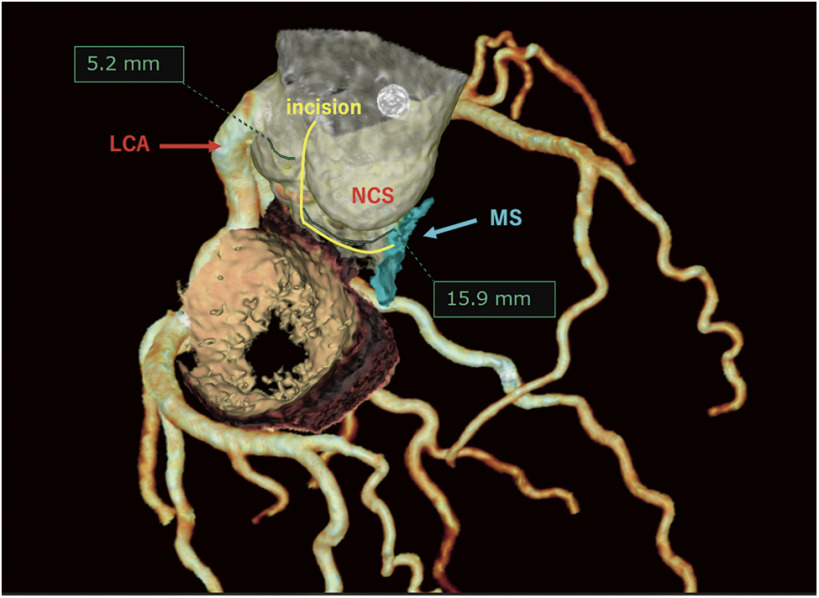

Bo博士在2021年推出的Y形切口技术是一种非常创新的技术,可以在不侵犯左心房或二尖瓣的情况下将主动脉瓣环扩大两个或两个以上的尺寸。然而,我们遇到了一个病例,其中左冠状动脉口位于左侧非连合附近。因此,我们认为将切口扩大到左冠状动脉环是危险的。因此,我们设计了一种新技术,只以“L”方式而不是“Y”方式放大非冠状环。在进行该手术时,术前三维图像有助于在计划主动脉环扩大手术时了解解剖结构。L形切口技术可能是主动脉瓣环扩大的一种有用的替代方法。

The Y-incision technique introduced by Dr. Bo Yang in 2021 is a very innovative technique that can enlarge the aortic annulus by two or more sizes without violating the left atrium or mitral valve. However, we encountered a case in which the left coronary artery ostium was located close to the left-non commissure. Therefore, we considered it would be dangerous to expand the incision to the left coronary annulus. We therefore devised a new technique that enlarges only the noncoronary annulus in an "L" fashion instead of a "Y" fashion. In performing this surgery, preoperative three-dimensional images were useful for understanding the anatomy when planning the aortic annular enlargement procedure. The L-incision technique can be a useful alternative method of aortic annulus enlargement.